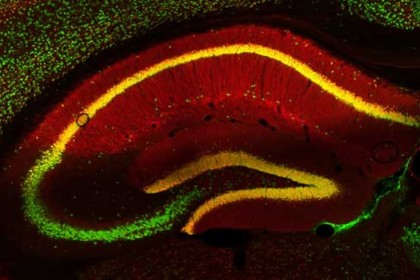

foto: Celulele nervoase ale creierului unui șoarece (verde) și proteina PRG-1 (roșu). Dacă celulele nervoase conțin PRG-1, celulele apar în galben. © Johannes Vogt